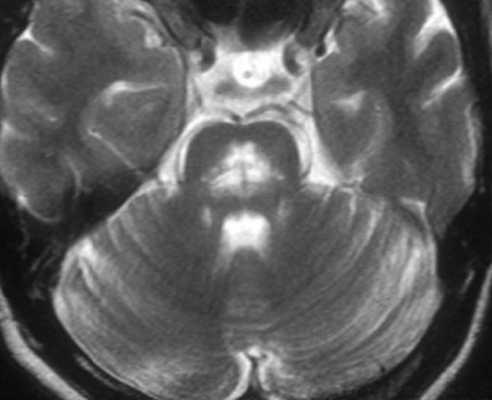

МРТ-исследование проведено на магнитно-резонансном томографе «Siemens» с напряженностью магнитного поля 1,5 Тл, с получением стандартных Т1- и Т2-взвешенных изображений (Т1-ВИ, Т2-ВИ) в фронтальной, аксиальной и сагиттальной плоскостях, с последующей оценкой визуальных изменений головного мозга (см. рисунок). Выявлены признаки атрофии среднего мозга с симптомами колибри в сагиттальной (см. рисунок, а) и Микки Мауса в аксиальной плоскостях (см. рисунок, б).

МРТ головного мозга 79-летней пациентки с ПНП.

а — Т1-взвешенное изображение, сагиттальная плоскость. Атрофия среднего мозга, сохранение объема моста и атрофия крыши среднего мозга. Симптом клюва колибри; б — Т2-взвешенное изображение на аксиальном срезе на уровне среднего мозга. Атрофия среднего мозга с формированием симптома Микки Мауса.

Учитывая прогрессирование заболевания в течение года, с постуральными нарушениями, акинетико-ригидным синдромом, параличом взора, дизартрией, умеренным когнитивным нарушением, стереотипными поведенческими нарушениями, данные МРТ головного мозга (атрофия среднего мозга), а также недавно возникший оромандибулярный гиперкинез на фоне приема противопаркинсонического препарата, выставлен диагноз «ПНП с леводопа-индуцированной дискинезией в виде оромандибулярного гиперкинеза».